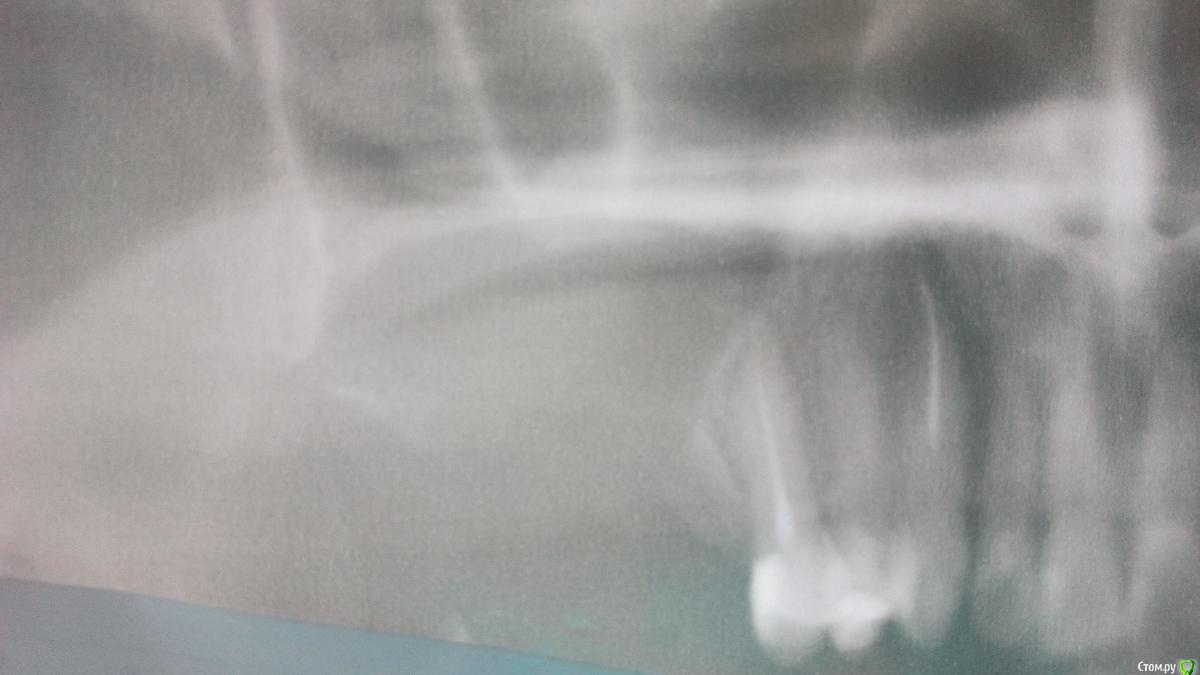

На7На Опубликовано 25 марта, 2018 Поделиться Опубликовано 25 марта, 2018 Здравствуете. Месяц назад была проведена операция цистэктомия, удаление 6, 7, 8 зубов. Киста была 28 мм х 23 мм. Перфорации не было как сказали, в пазуху не заходили. Киста ее прогибала. Зажило все хорошо. Швы сняли. Но больно нажимать на 5 зуб. Даже если языком сверху нажать больно. Не говоря уже что-то откусить. Сегодня сделала снимок. Зуб пролечен хорошо. Я не знаю что делать. Ссылка на комментарий

Irouil Опубликовано 25 марта, 2018 Поделиться Опубликовано 25 марта, 2018 Да снимки все сегодня. Перелечивать 5? Сегодня врач смотрел по снимку сказал хорошо пролечен, но он может давить на пазуху. Может поэтому боль?Может, но месяц боли после операции - долговато. Реабилитация там должна была уже пройти. К сожалению плоскостные снимки обладают ограниченной информативностью. В такой ситуации как у Вас их можно интерпретировать двояко: не будь у Вас жалоб на боли, я бы тоже сказал, что наверное все хорошо. Я, все же, рекомендую 3д КЛ КТ. Верхнюю челюсть и верхнечелюстные пазухи, 12х8.5 хватит. Ссылка на комментарий

На7На Опубликовано 25 марта, 2018 Автор Поделиться Опубликовано 25 марта, 2018 Может, но месяц боли после операции - долговато. Реабилитация там должна была уже пройти. К сожалению плоскостные снимки обладают ограниченной информативностью. В такой ситуации как у Вас их можно интерпретировать двояко: не будь у Вас жалоб на боли, я бы тоже сказал, что наверное все хорошо. Я, все же, рекомендую 3д КЛ КТ. Верхнюю челюсть и верхнечелюстные пазухи, 12х8.5 хватит.Мне еще сегодня сказали что между пазухой и десной нет кости. Что ее надо закрывать . Надо ли это делать? Там же нарастает железистая ткань, заполняет эту пустоту. Ссылка на комментарий